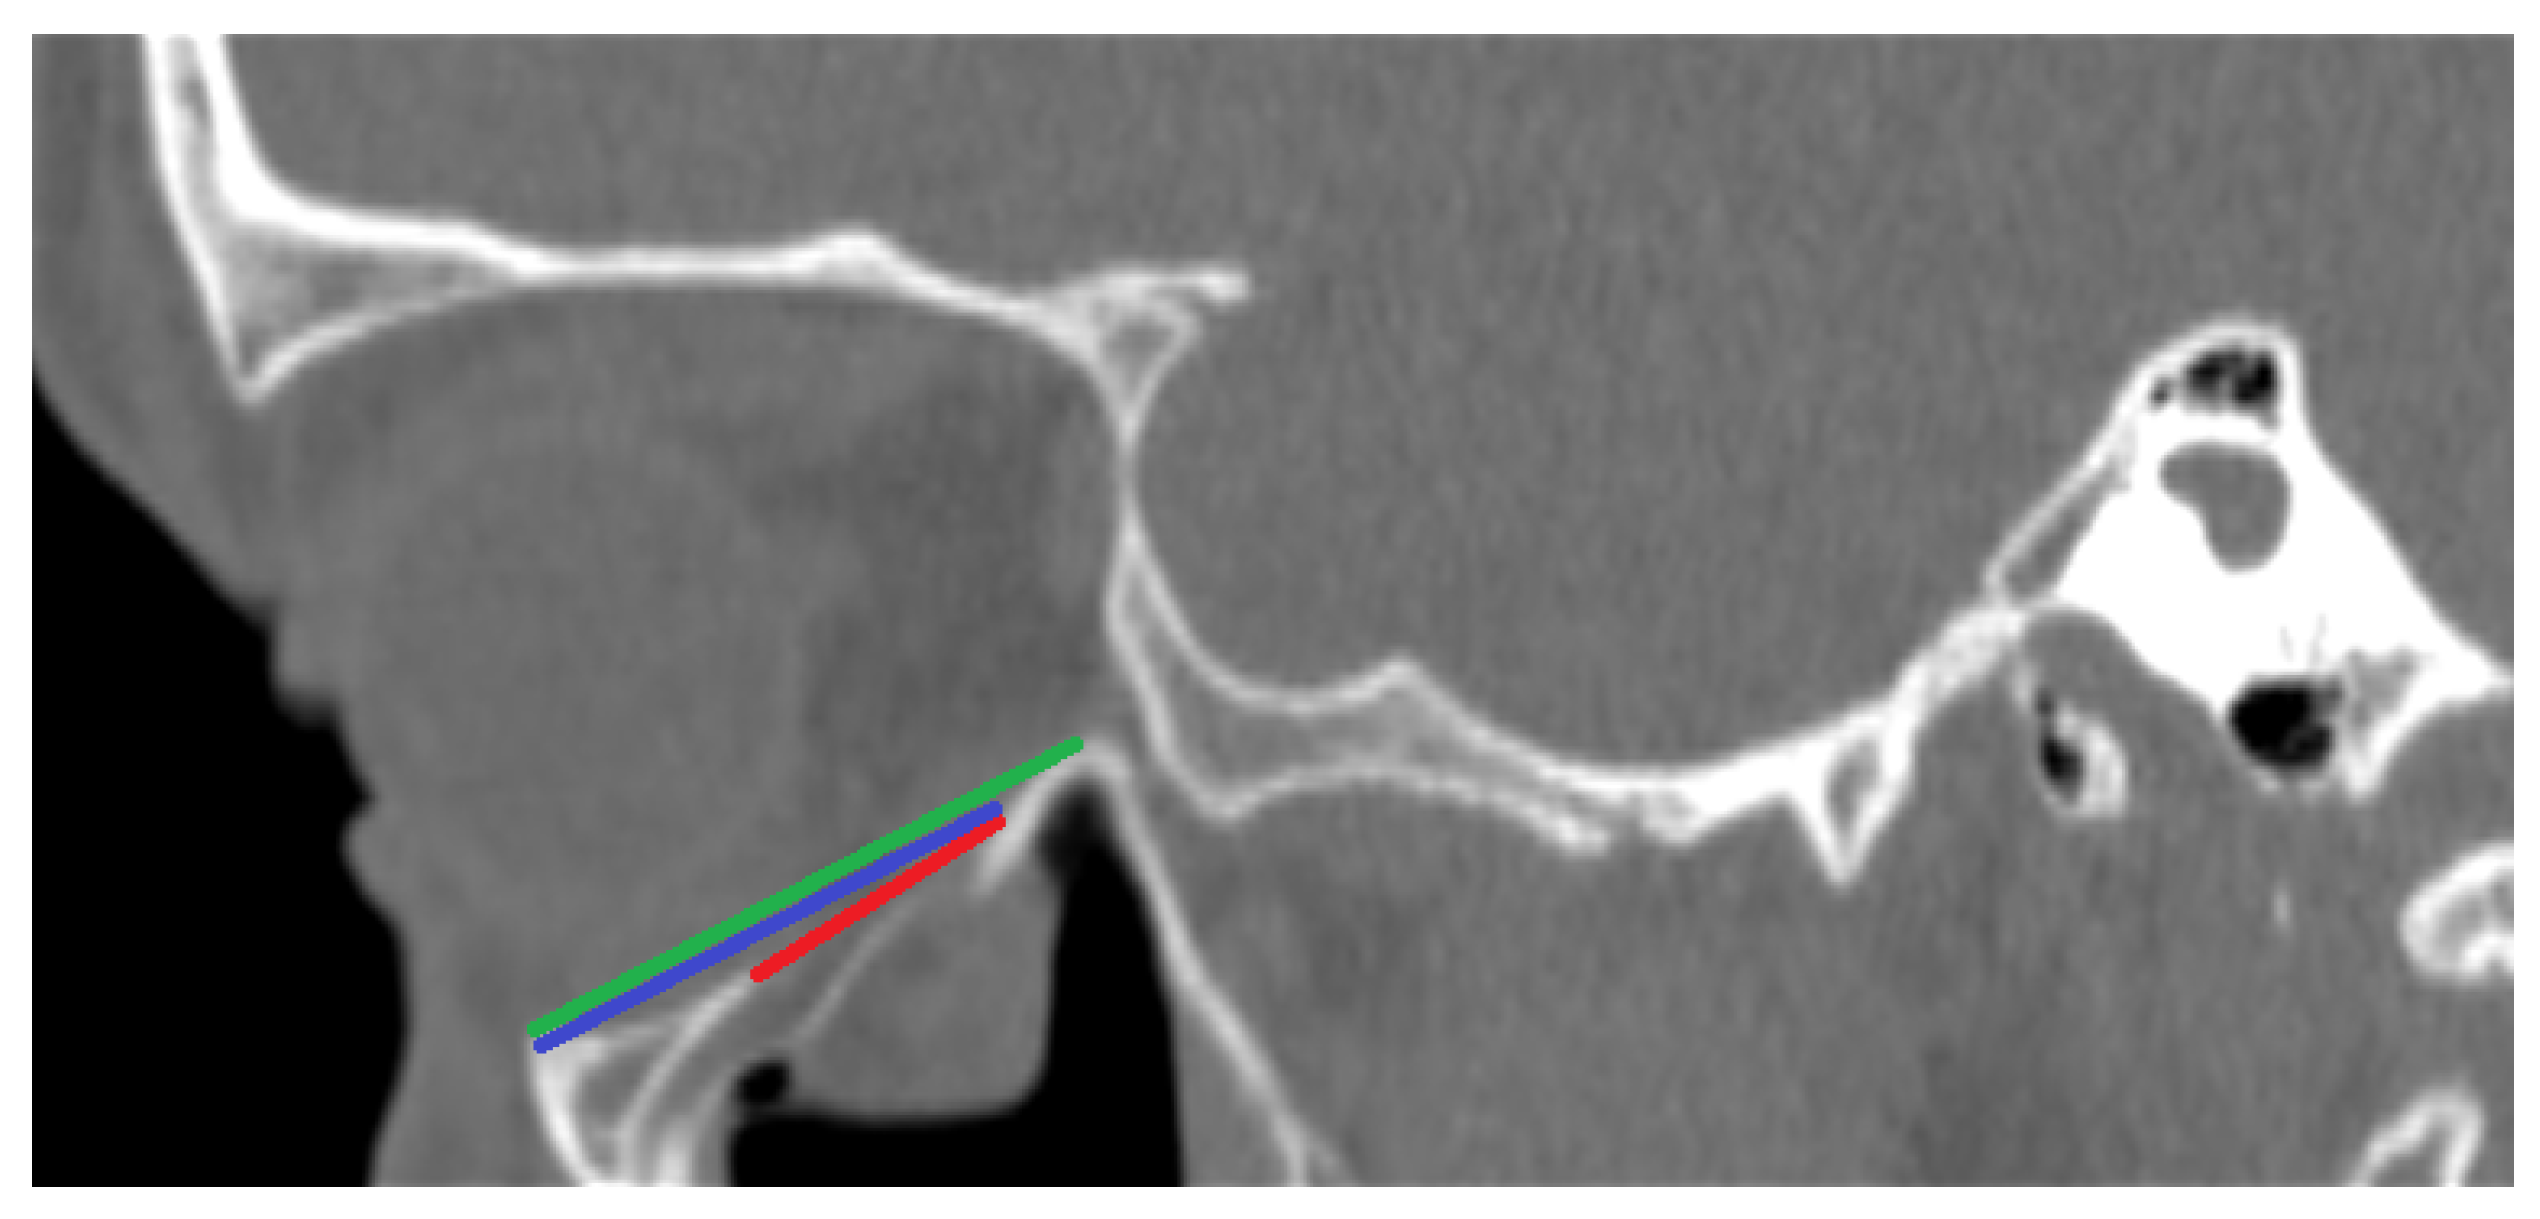

- PI—Largest length of the fracture in the sagittal plane in millimeters (See Figure 1);

- PII—Distance between the end of the fracture and the infraorbital margin in the sagittal plane in millimeters (See Figure 1);

- PIII—Distance between the infraorbital margin and the end of the orbit in the sagittal plane in millimeters (See Figure 1);